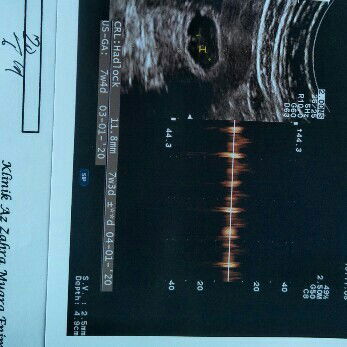

usg

bunda normal kah panjang ukuran janinnya yah .. ???